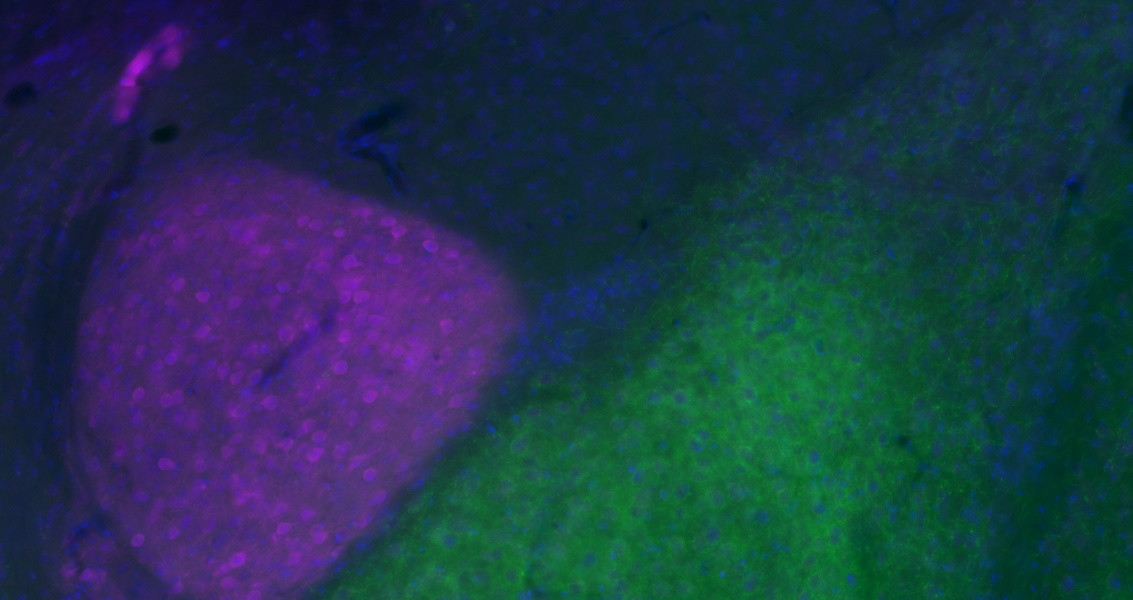

Az amygdala kapcsolatrendszere

Az amygdala - az egyik legintenzívebben kutatott agyterület –, egy rendkívül összetett, agykérgi és kéreg-alatti elemekből álló hálózat központi eleme. Fontos szerepet játszik az érzelmek szabályozásában és a tanulásban, de olyan pszichiátriai megbetegedésekkel is kapcsolatba hozták, mint a szorongás vagy a poszt-traumás stressz.

Laborunkban ezért azon dolgozunk, hogy jobban megértsük az amygdala belső- és külső kapcsolatrendszerét, amihez különböző neuroanatómiai és elektrofiziológiai módszereket használunk fel. Reményeink szerint kutatásaink hosszú távon hozzájárulnak ahhoz, hogy az amygdalával kapcsolatos, ma még megválaszolatlan kérdések megoldódjanak.

Az amygdala szépségei